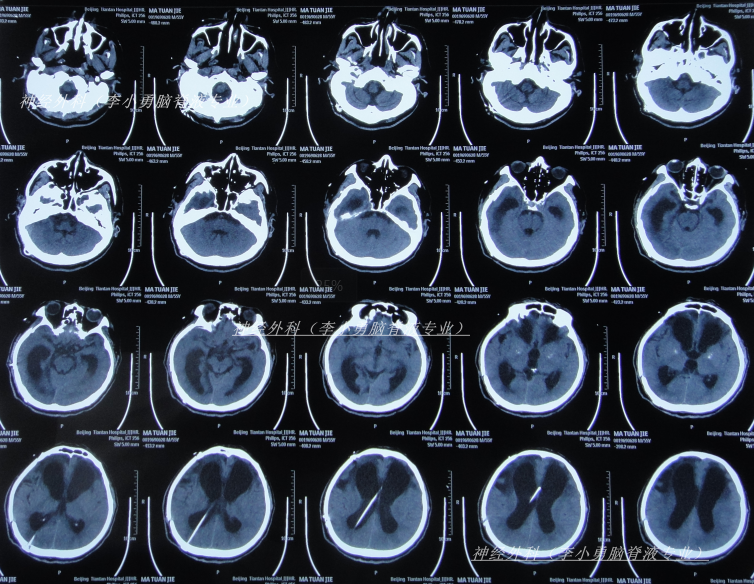

因症状没有改善,决定到北京就诊,经过考虑在李小勇脑脊液专业和北京某三甲医院,选择了北京某三甲医院,2025年1月10日(颅骨修补术后85天即脑室腹腔分流术后113天),住入北京某三甲医院,查头颅CT(图-6)和腰穿检查后考虑颅内感染,给予抗感染治疗。

图-6:2025年1月10日头颅CT

治疗4天后即2025年1月13日,仍发热,查头颅CT(图-7)和肺部CT(图-8)后继续抗感染治疗。

图-7:2025年1月13日头颅CT